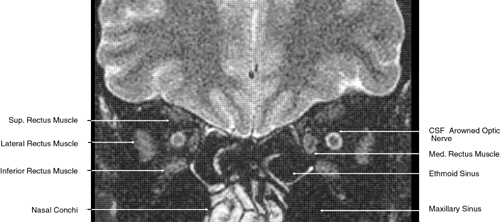

The globe is shown in Figure 12. The orbit and periorbital structures are shown in Figures 13 through 16, and the optic canal is shown in Figures 17 through 26. The cavernous sinus and optic chiasm are shown in Figures 27 and 28, and the posterior visual pathway and cranial nerves are shown in Figures 29 through 33.

Fig. 22. Axial images at the level of inferior orbit. A. Computed tomography scan. B. T1-weighted magnetic resonance imaging.

Fig. 23. Axial images at the level of midorbit. A. Computed tomography scan. B. T1-weighted magnetic resonance imaging.

Fig. 24. Axial images at the level of superior orbit. A. Computed tomography scan. B. T1-weighted magnetic resonance imaging.

Fig. 25. Axial images at the level of tendon of the superior oblique. A. Computed tomography scan. B. T1-weighted magnetic resonance imaging.